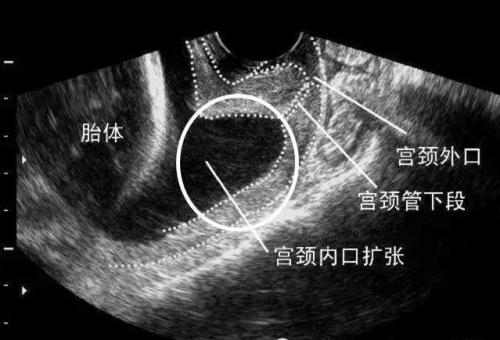

正常的宫颈形态呈“T”形,宫颈内口是关闭的。而宫颈机能不全随妊娠进展,胎儿生长、羊水增多导致宫腔压力增多,宫颈明显缩短、松弛、扩张,宫颈内口逐渐由“T"形,转变为“Y”形、“V"形、“U”形,从而导致流产或早产。当宫颈内口呈“V"形、“U”形扩张时发生早产风险更高。